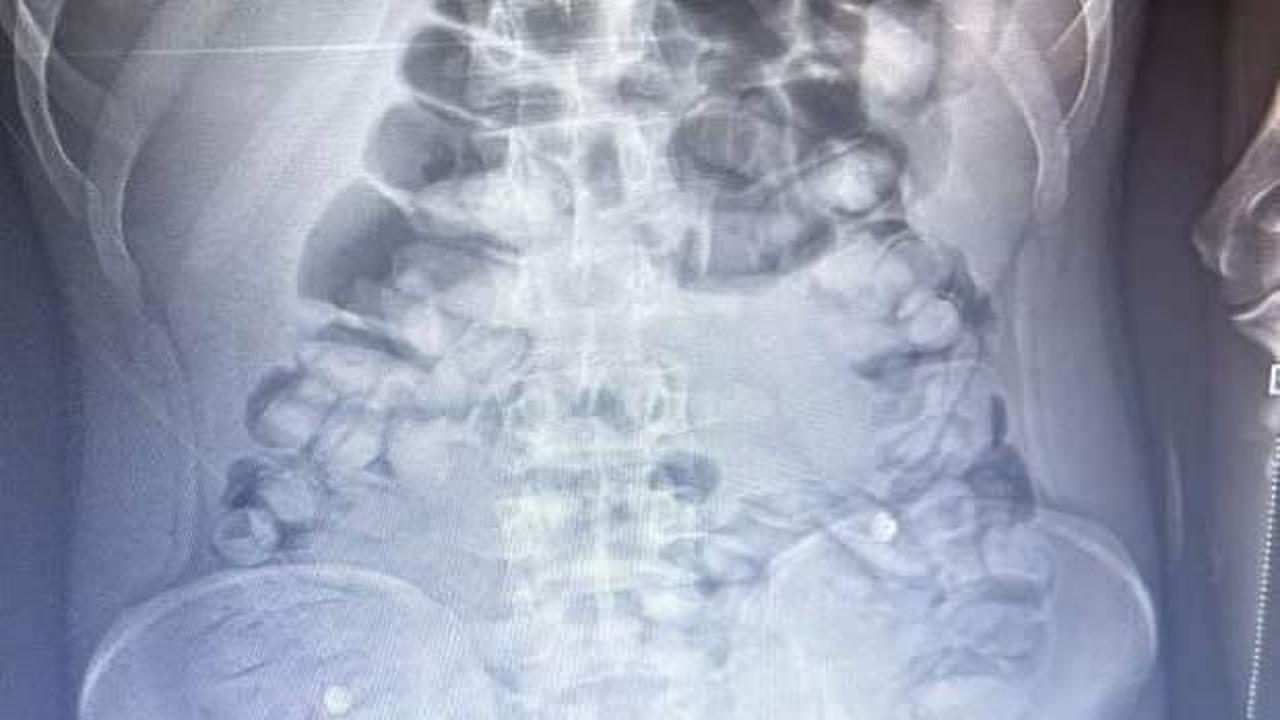

Erzurum’da, yolcu otobüsünde şüphe üzerine hastanede röntgeni çekilen yolcunun midesinde Afyon sakızı, tespit edildi. Yolcu, midesindeki 1 kilo 134 gram Afyon sakızını doğal yollarla çıkardı.

İl Emniyet Müdürlüğü Narkotik Suçlarla Mücadele Şube Müdürlüğü ekipleri, bir yolcu otobüsünde yaptığı denetimde, durumundan şüphelendiği yolcuyu hastaneye götürdü. Burada rdöntgeni çekilen yolcunun midesinde uyuşturucu tespit edildi. İlaç verilen yolcu, 1 kilo 134 gram Afyon sakızını doğal yollarla çıkardı.